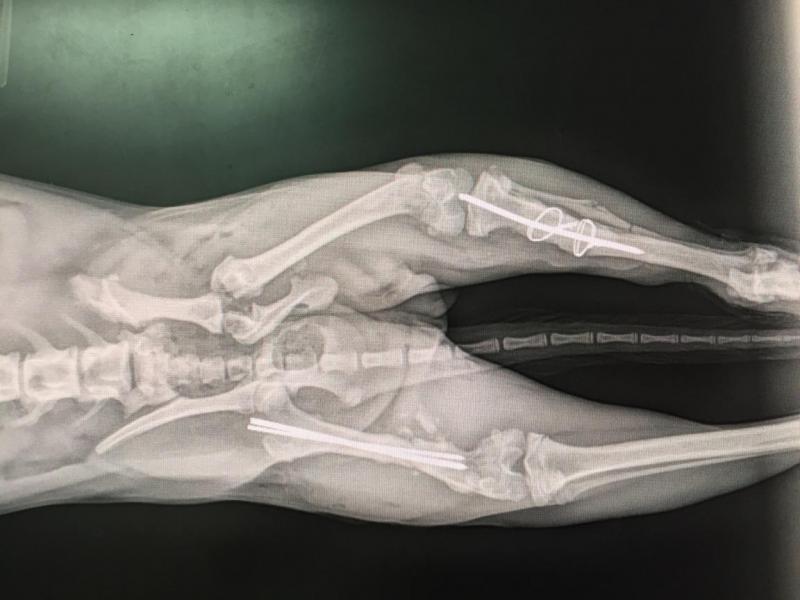

Canine, month-old fracture repair

Bone plating, Feline

Radius ulna fracture, Italian greyhound

Orthopedic repair, canine hit by car, hind legs fractured